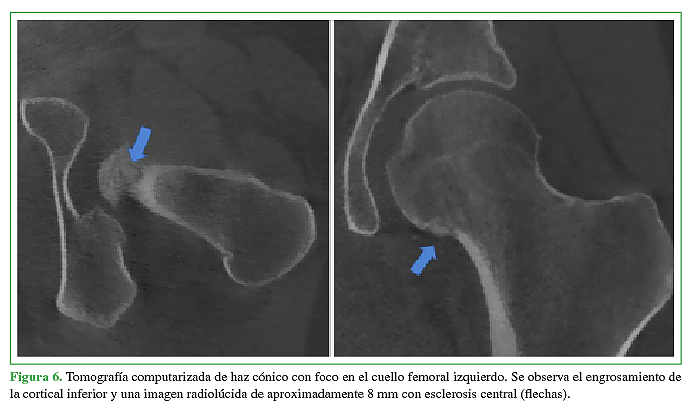

Se presenta un caso de un paciente femenino de 22 años con dolor en cadera izquierda de larga evolución sin antecedentes reelevantes.Descargas